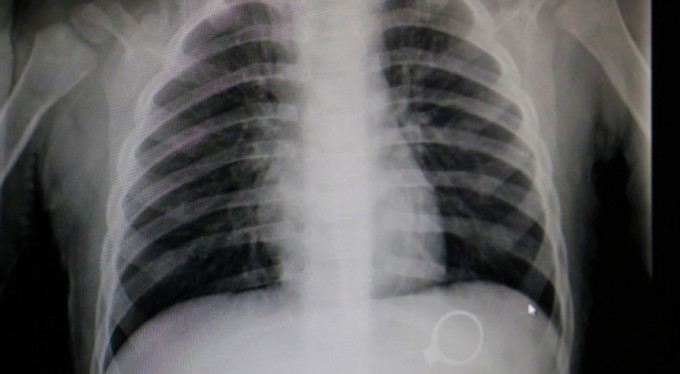

Sivas'ta kent merkezinde yaşayan F.G. ve C.G. çiftinin 1.5 yaşlarındaki M.G adındaki bebekleri oynamak için annesinden tek taş yüzüğünü istedi. Yüzükle oynayan M.G. annesine fark ettirmeden yüzüğü yuttu. Bir süre sonra çocuğunun yüzüğü yuttuğunu fark eden anne çocuğunu kucaklayarak Sivas Medicana Hastanesine götürdü. Burada Çocuk Cerrahisi Uzmanı Op.Dr. Mahmut Aluç tarafından muayene edildi. Yüzüğün, röntgeni çekilen M.G'nin midesinde olduğu görüldü. 6 gün sonra yüzük doğal yollarla çıktı. Çıkan yüzük aileye rahat bir nefes aldırdı.

Röntgende belli oldu

Çocuk Cerrahisi Uzmanı Op.Dr. Mahmut Aluç, çekilen röntgende yüzüğün midede olduğunu belirlediklerini ifade ederek, "Hastamız 1 buçuk yaşında. Bundan 6 gün önce bize yüzük yutma şikayeti ile başvurdu. İlk çektiğimiz grafide yüzüğün mide de olduğunu saptadık ve aileyi bilgilendirdikten sonra rutin prosedürlerinin gereği beklemeye başladık. 6 gün sonra spontane olarak yüzüğün kendisi çıktı. Bu tür hastalarla oldukça sık karşılaşıyoruz. Rutin olarak şöyle bir kural vardır, çocuk ağzına aldığı her şeyi yutabilir. Özellikle küçük çocuklar cisimleri tanımak için elleriyle dokunduktan sonra genellikle ağızlarına alırlar. Bu yutulan cisimler toplu iğne olabilir, çengelli iğne olabilir, para olabilir" dedi.